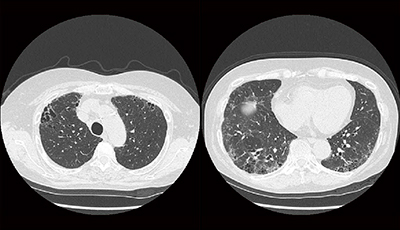

胸部単純X線写真では,上肺野優位の網状影,浸潤影が認められる。単純CT画像(図4)では,上肺野に強い網状影とコンソリデーションが認められた。胸部X線動態画像(図5)では全体的に動きが悪く,横隔膜の動きも不自然で,側面像では肺の下葉が呼吸を支えているという印象である。変位のベクトル表示画像(図6)でも肺野全体の動きが悪い印象であった。

図4 症例2:胸部単純CT画像